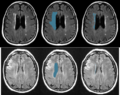

We are developing methods for segmentation of white matter hyperintensity (WMH) in FLAIR images of stroke patients. Specifically, WMH is to be localized in particular areas of the brain, as seen in a training set. This dataset is particularly challenging due to the low resolution (1mm x 1mm x 7mm) and with cropped fields of view in the given images.

• We wrote and tested some classification methods using SVMs with RBF kernels based on intensity features. We currently don't impose a smoothness constraint, but can optionally run a slight smoothness pre-processing step.